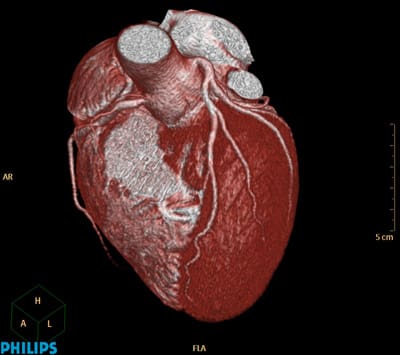

The need for speed continued to push CT machine designers, especially in the medical area. CT scanners for imaging the heart are especially challenging, because of the natural motion of the beating heart. This procedure, known as Cardiovascular Computed Tomography Angiography (CCTA) is a growing application. In this case, the X-ray equipment needs to get around the heart between beats, while the heart is at rest, in order to image the fine blood vessels feeding blood to the heart muscle itself (Figure 2). There are only two options: slow down the heart through sedation or speed up the rotation of the machine.

Philips Healthcare, a major supplier of CT equipment began a new machine design with a fresh sheet of paper in order to find a way to speed up the rotation. According to Philips Healthcare CT Product Manager Robert Popilock, their clinical partners were “interested in performing CT examinations of the heart, requested a system capable of faster rotation speed to improve the likelihood of capturing a “snapshot” (Figure 3) of the vessels supplying blood to the heart wall at the most quiet state.1 ” The solution they found also solved many of the other problems of building precision CT scanning equipment.

Philips Healthcare started with their fresh design effort early in the 21st century knowing they needed to increase scanner speeds. Air Bearing support had the speed and other advantages they were interested in. Ultimately, they selected porous carbon air bearing technology from New Way Air Bearings, who worked with them through a six-year development. In November 2007, Philips introduced the Brilliance iCT Scanner at the Radiological Society of North America Annual Meeting using “AirGlide” technology. Today, there are over 1,000 Brilliance iCT Scanners in the field using New Way Air Bearings with an excellent reliability record.